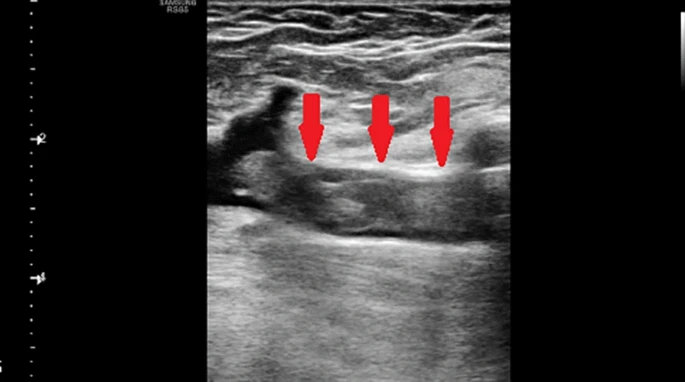

Ultrasound in the diagnosis of acute-phase decompression sickness